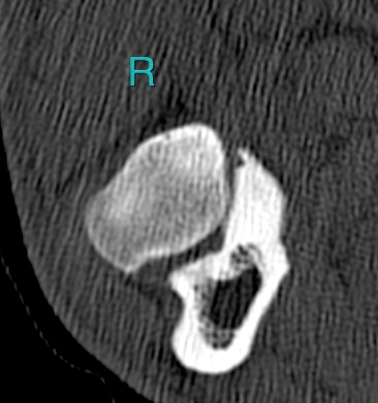

- I really don’t know what we’re looking at on this part of the ct scan. Other than it’s Pasha’s right.